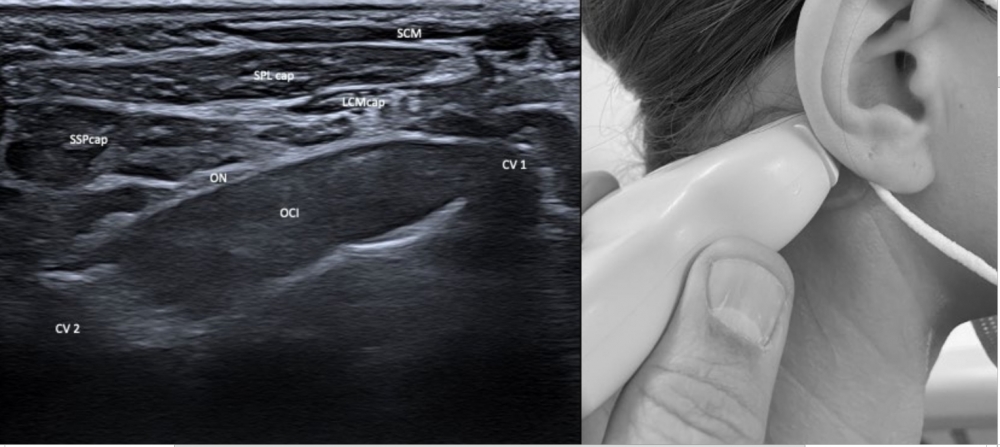

ULTRASOUND OF CERVICAL DYSTONIA Superficial Layers: TRA: Trapezius

Deep Layers SCM: Sternocleidomastoid CV1 & 2: Atlas and axis vertebrae

|

LATERAL

POSTERIOR Superficial

Intermediate

Deep